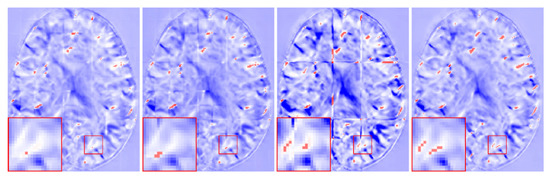

From Table 4, it can be observed that the distance functions have little difference in the quantitative analysis. We also show the fusion results of the three distance functions in Figure 11. From the top row, we can see that the slices in the middle of the DDF introduced the three distance functions without grid-like artifacts. However, the Chebyshev distance still has a significant seam at the edge slice seen on the bottom row. In Figure 4, when using the Chebyshev distance as a distance function, the distances from the points at the edge to the centroid are equal. This gives the same weight to all predicted values at that point no matter how many times they overlap, which results in grid-like artifacts still appearing at the edge. Combined with Figure 5, the Chebyshev distance appears to undulate in the transition from low to high frequencies, which indicates that it is less stable at the edge and will retain some high-frequency information. Therefore, by our method, introducing the Euclidean distance or Manhattan distance can obtain the DDF without grid-like artifacts.

Figure 11.

DDFs of three distance functions at 100 slices (a) and 160 slices (b) of the axial plane. The 1st column is the Chebyshev distance, the 2nd column is the Manhattan distance, and the 3rd column is the Euclidean distance.